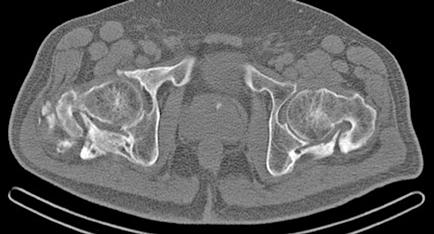

Es ingresado en Medicina Interna en mayo de 2022 por cuadro de fiebre de origen no filiado acompañado de astenia crónica y artralgias múltiples (especialmente en hombro izquierdo). Se administra ceftriaxona intravenosa con buena evolución del proceso febril. No se aísla ningún microrganismo en estudio microbiológico. En el análisis sanguíneo al ingreso destacan los siguientes valores: Hemoglobina 9,1 g/dL; Volumen Corpuscular Medio 105,5 u^3; Leucocitos 8200/L; Neutrófilos 6900/L; Plaquetas 64000/L. En la morfología de sangre periférica se observaban hematíes en lágrimas. Se realiza tomografía computarizada toracoabdominal en el que destaca esplenomegalia de 14 cm, quiste hidatídico hepático y múltiples nódulos milimétricos en ambos lóbulos pulmonares inferiores (Figura 1).

Ha necesitado ingresar recientemente por una fractura de cadera derecha que requirió intervención quirúrgica por parte de Traumatología en contexto traumatismo por síncope. Además, presenta síndrome febril sin aislamiento microbiológico ni foco filiado que mejora tras tratamiento antibiótico con ceftriaxona y levofloxacino. Destaca al ingreso trombopenia severa con 28000/L plaquetas que tras intervención y resolución de proceso infeccioso remontan hasta 137000/L (Figura 4).